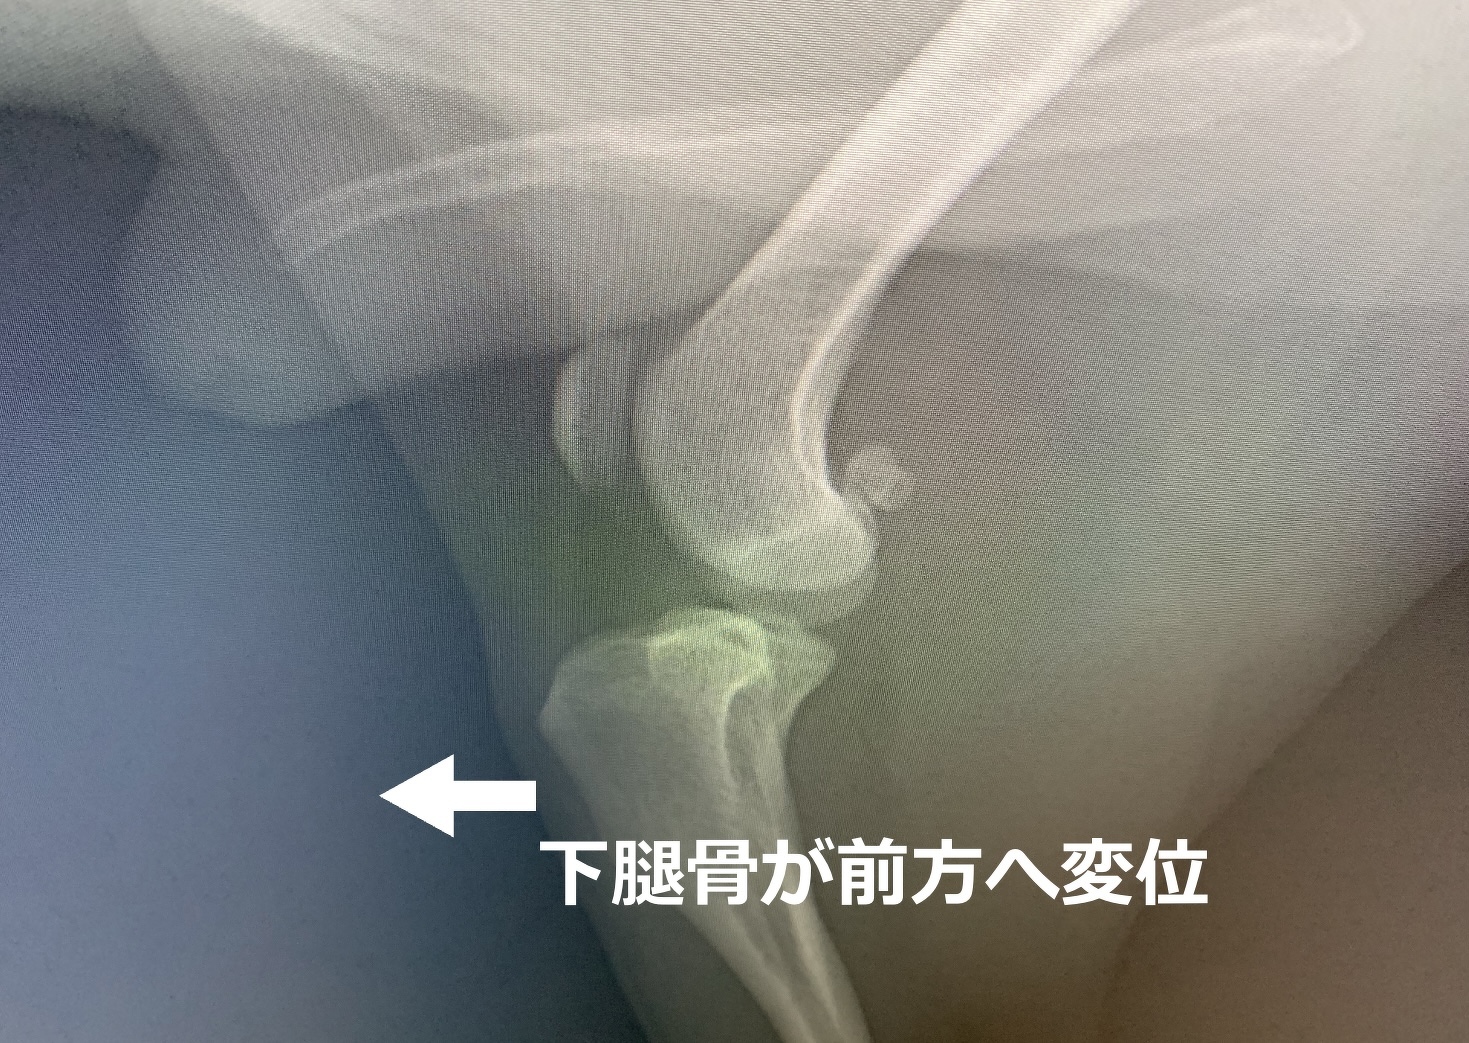

今回は、犬の十字靭帯損傷についてお話ししたいと思います。犬は活発で運動が大好きな動物ですが、時にはケガをしてしまうこともあります。特に十字靭帯損傷はよく見られる症状の一つです。

十字靭帯損傷を起こした犬は、以下のような症状が見られることがあります。

1. 跛行(はこう): 損傷したどちらかの後肢をあまり使わず、かばっているように歩きます。時に足をつくことが全くできなくなります。

2. 痛み: 損傷した靭帯が炎症を起こすため、犬は触られると嫌がることがあります。十字靭帯損傷の場合、痛みというよりも、損傷している後肢に体重を乗せることに違和感を感じているような破行なので、キャンキャンいうような痛みを感じることは少ない印象です。

3. 腫れ: 損傷がひどく、関節炎を合併しているときは患部(膝)が腫れることがあります。

4. 安静時の関節の不安定感: しばしば患部の関節が不安定になり、犬が無理な動きを避けるようになることがあります。

十字靭帯損傷の主な原因は、犬が激しい運動をしたり、ジャンプしたりする際に、足を不自然な方向にねじったり、急に止まったりすることです。特に大型犬やスポーツ犬種、角に肥満している犬は、この損傷の高いリスクにさらされる場合があります。また、小型犬種で膝蓋骨内方脱臼症という膝のお皿の骨(膝蓋骨)が内側に入りやすい、O脚の傾向のあるワンちゃんは、その膝の形状によって前十字靭帯に負荷がかかりやすく、靭帯損傷や断裂が起こりやすいと考えられています。